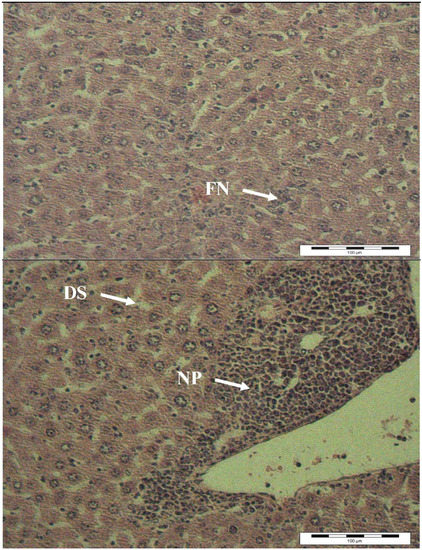

2.4. Histopathology Analysis